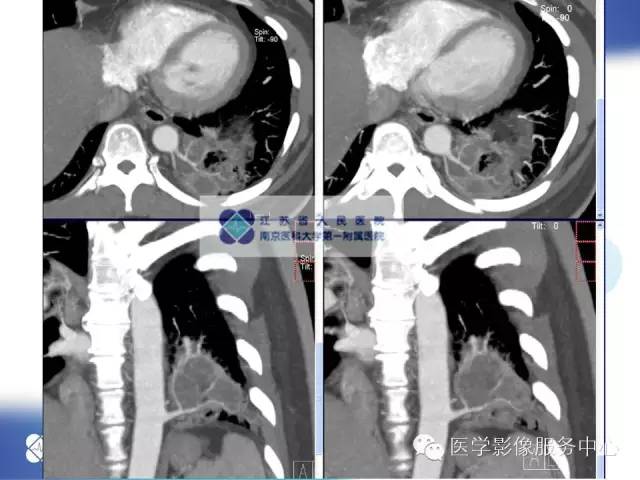

【病例】肺隔离症1例CT影像表现

女性,36岁。反复发热、咳嗽、咳痰一年。

本病例较典型,结合图像后处理技术( MPR、MIP、VR)可以确诊!

CT:主要表现为三种类型:含有气体和液体的囊肿或软组织肿块;围绕囊肿或肿块周围的肺气肿改变;局限性肺多血管征。病变周围肺组织还可伴有支气管扩张,肺组织实变等。增强扫描病变实质可见轻度或明显不规则强化,囊性病灶可见环形强化,结合图像后处理技术( MPR、MIP、VR)多可见异常供血动脉及引流静脉,在一定程度上可以取代动脉造影。隔离肺组织供血动脉多为胸主动脉和腹主动脉,少数为隔下动脉、肋间动脉、脾动脉等。引流静脉多为肺静脉。